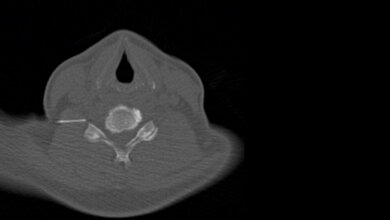

CT-gestützte Punktionen

Ableitung von Flüssigkeiten und Gewinnung von Gewebeproben

Einleitung: Für die CT-gestützte Intervention gibt es eine Reihe verschiedener Indikationen. Diese umfassen exemplarisch die Biopsie von sonografisch schwer erreichbaren Körperregionen für histopathologische Begutachtungen und die Drainage von Flüssigkeitskollektionen.

Insbesondere im Hinblick auf die Drainage entzündlicher Flüssigkeitskollektionen kann eine minimalinvasive, CT-gestützte Intervention häufig einen operativen Eingriff ersetzen. Dieser Artikel soll die ärztlichen und assistierenden Tätigkeiten zeigen und einen Überblick über die CT-gestützte Biopsie und Drainage geben.